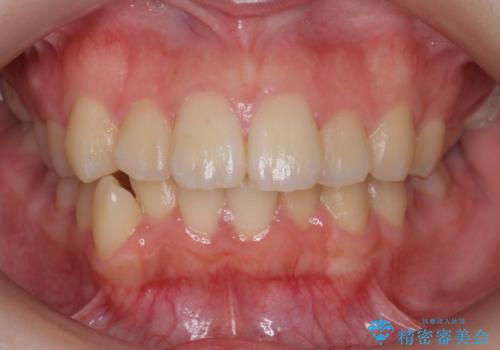

- 歯のがたつきを主訴に来院。

左右とも奥歯のがたつきがあり、左奥はすれ違っていました。

また、右奥は反対咬合になっていました。

インビザライン治療は主に奥歯のかみ合わせが大きな問題がない場合は特に問題なく終了しますが、今回のケースのように奥歯のかみ合わせが悪い場合、しっかり治らないことがあります。

患者様が気づかない範囲で妥協して終わるということをせず、しっかり奥歯に部分矯正を用いて大きな問題を解決してからインビザライン治療に入りました。

下の前歯を一本抜歯しています。(抜歯の本数は最小限にしています。)